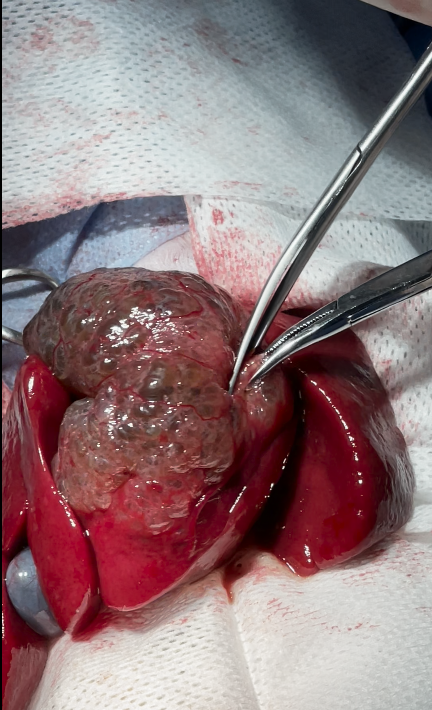

Hepatobiliary (or biliary) cystadenoma is a benign epithelial neoplasm originating from the intrahepatic or extrahepatic bile ducts. It is characterized by multiloculated cystic masses lined by biliary-type epithelium and often filled with serous or mucinous fluid

Microscopic examination of the hepatic tissue revealed multiple cystic structures lined by a single layer of cuboidal to columnar epithelial cells resembling biliary epithelium. The cysts contained eosinophilic to lightly basophilic fluid and were separated by thin fibrous connective tissue septa.

The epithelial lining showed minimal to no cellular atypia

The surrounding hepatocytes were well differentiated, and there was no necrosis or inflammatory infiltration suggestive of malignancy.

These findings are consistent with a diagnosis of Hepatobiliary (Biliary) Cystadenoma — a benign cystic epithelial neoplasm of biliary origin